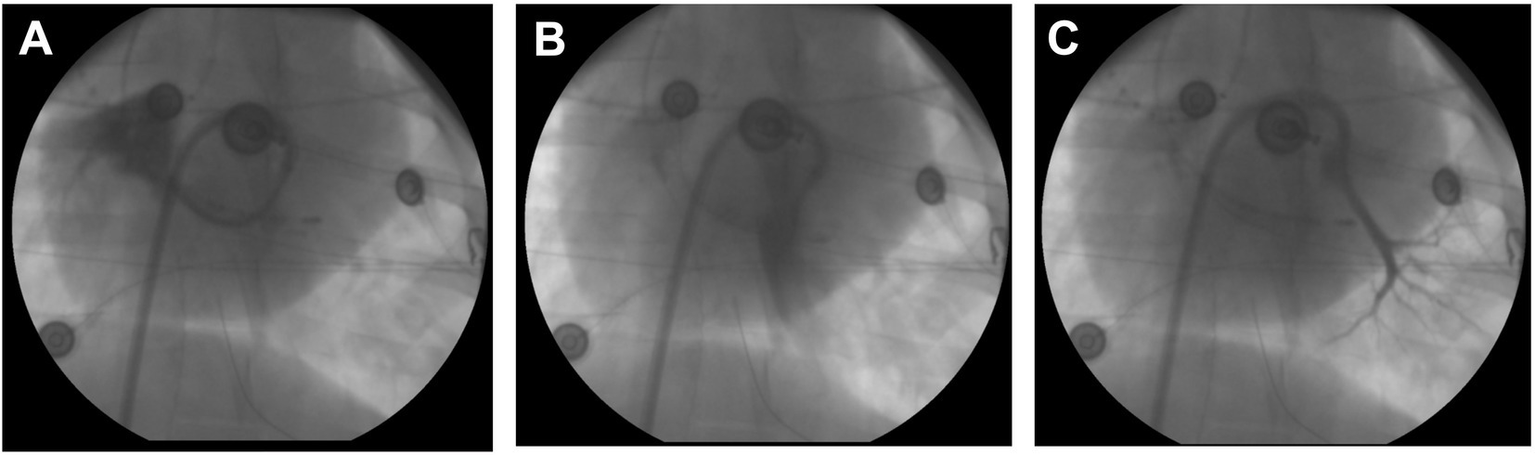

Figure 4

Pulmonary vein angiography. (A) Selective angiography of the right superior common ostium using a loop technique with steerable sheath and diagnostic catheter. (B) Angiography of the large inferior common trunk. (C) Angiography of the smaller left superior branch.

In animals with a patent foramen ovale, transseptal access was achieved by advancing the ablation catheter through the patent foramen ovale. In the remaining animals, the left atrium was accessed by a blunt puncture through the membranous part of the fossa ovalis. For illustrative purposes, selective pulmonary vein angiography was performed in a subset of animals displaying a small left superior pulmonary branch, a large inferior common pulmonary trunk, and a common trunk for the right inferior and right middle branches (Figure 4).